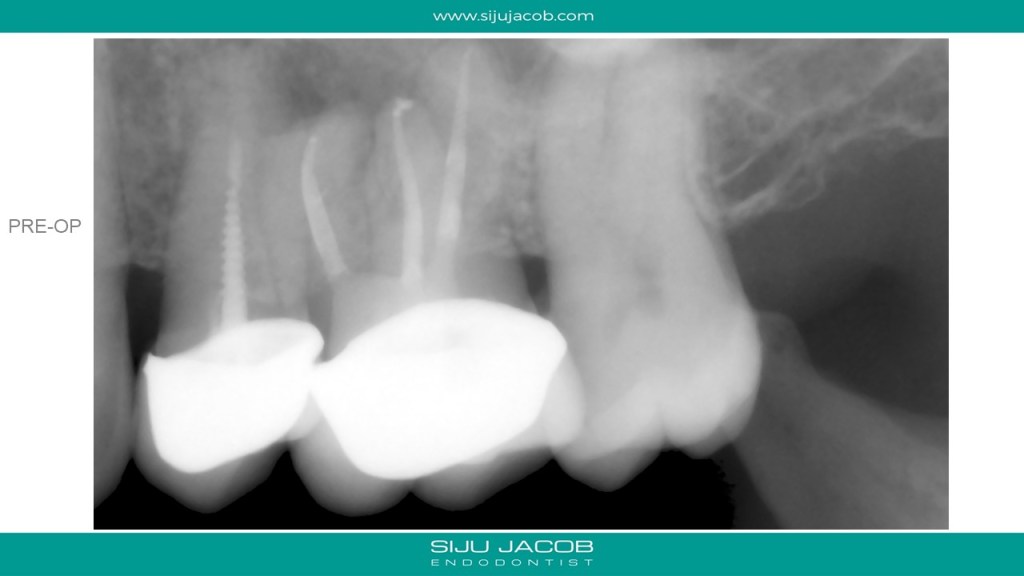

This is a Maxillary first molar treated several years ago and the patient came back with pain. CBCT shows missed MB2 with separate portal of exit. I located and treated only the MB2. Left the rest of the canals as they were.